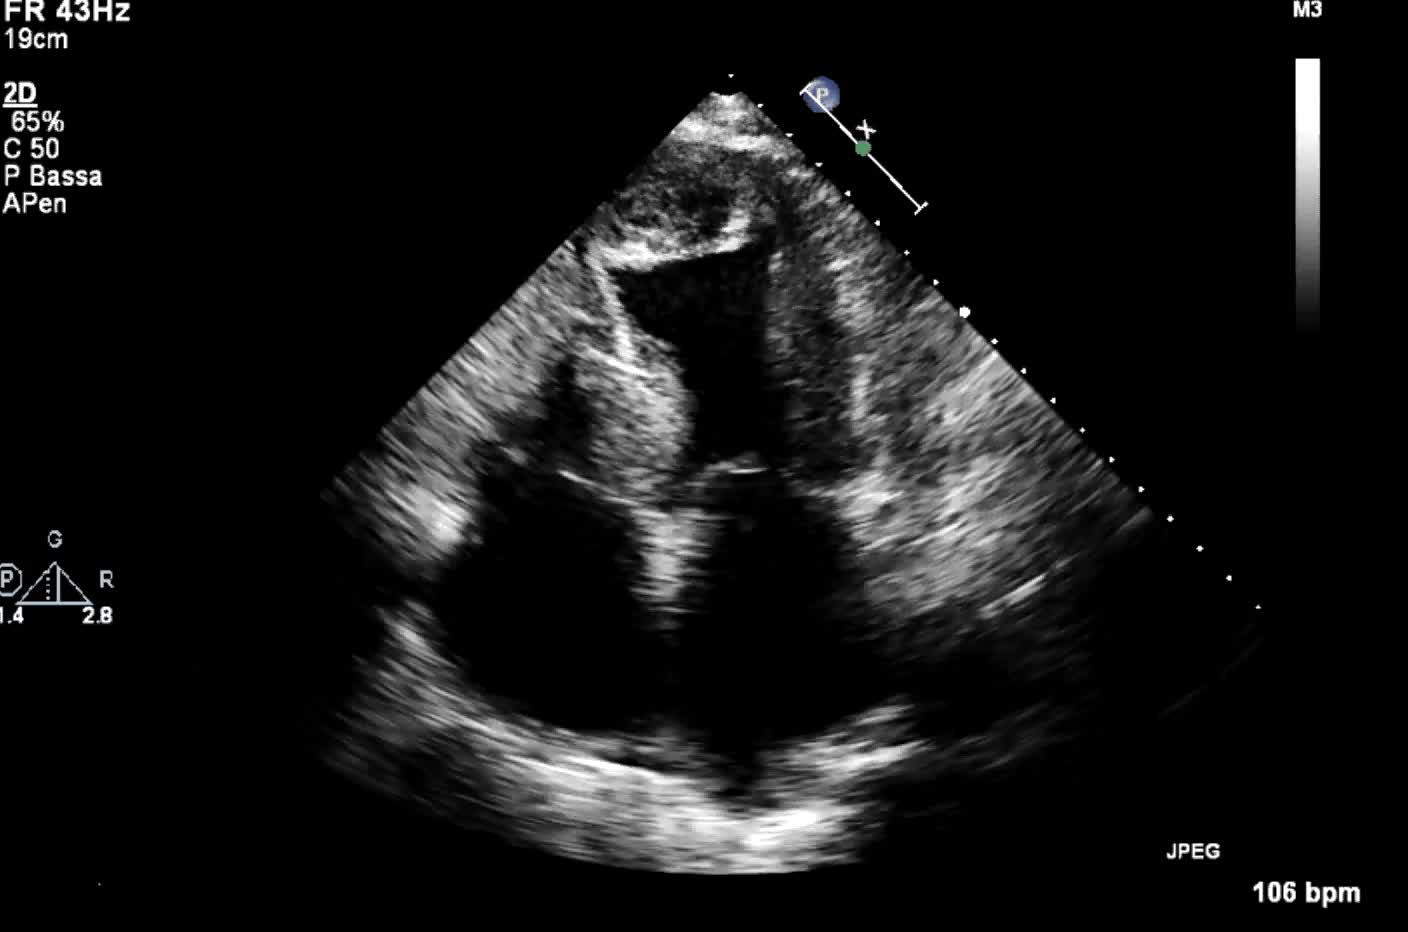

Titolo:

Autore: